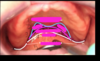

ID green

palatine aponeurosis (tensor veli palatini, levator veli palatini) palatopharyngeus, palatoglossus, and musculas uvale

ID 1

labial frenum